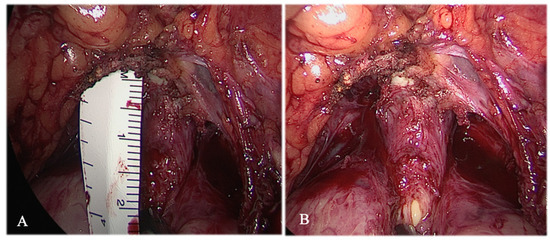

2.2. Procedures